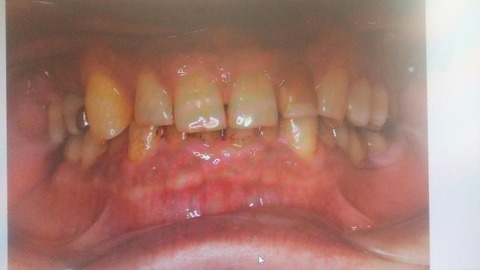

新しい病院へ行く。まずは、口の中の初期値の写真をとる。鏡のようなものをくわえて、裏側も取りました。いずれも、おぞましき写真です。歯の裏ヤニで真っ黒^^;^^;。